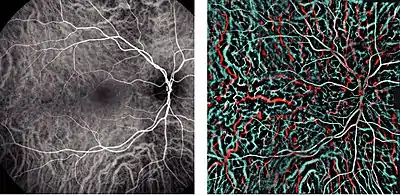

There are two circulations of the eye: the retinal (in the retina) and uveal, supplied in humans by posterior ciliary arteries, originating from the ophthalmic artery (a branch of the internal carotid artery).[2] The arteries of the uveal circulation, supplying the uvea and outer and middle layers of the retina, are branches of the ophthalmic artery and enter the eyeball without passing with the optic nerve. The retinal circulation, on the other hand, derives its circulation from the central retinal artery, also a branch of the ophthalmic artery, but passing in conjunction with the optic nerve.[3] They branch in a segmental distribution to end arterioles and not anastomoses. This is clinically significant for diseases affecting choroidal blood supply. The macula responsible for central vision and the anterior part of the optic nerve are dependent on choroidal blood supply.[4] The structure of choroidal vessels can be revealed by optical coherence tomography, and blood flow can be revealed by Indocyanine green angiography, and laser Doppler imaging.[5]

Schematic cross section of the human eye; choroid is shown in purple. Laser Doppler imaging of retinal and choroidal blood flow

Laser Doppler imaging of retinal and choroidal blood flow Iris, front view